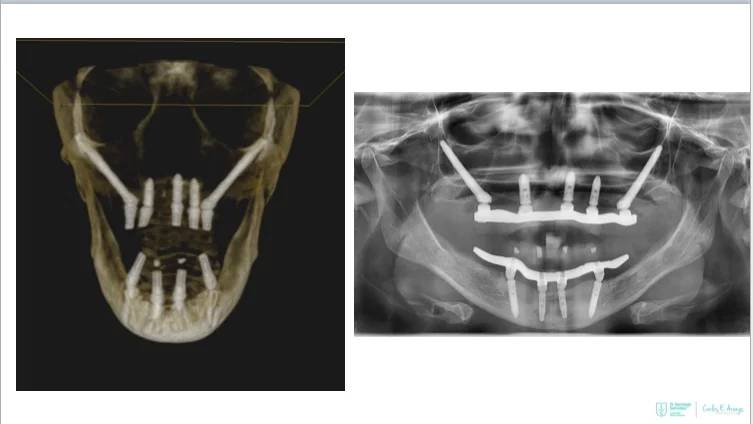

- Full-arch rehabilitation with only four implants

Two straight anterior implants and two implants tilted up to 45º in the posterior - Immediate Function (fixed provisional bridge)

For patients meeting criteria for immediate loading of implants - Graftless Procedure: Bone grafting is avoided by tilting the posterior implants, utilizing available bone.